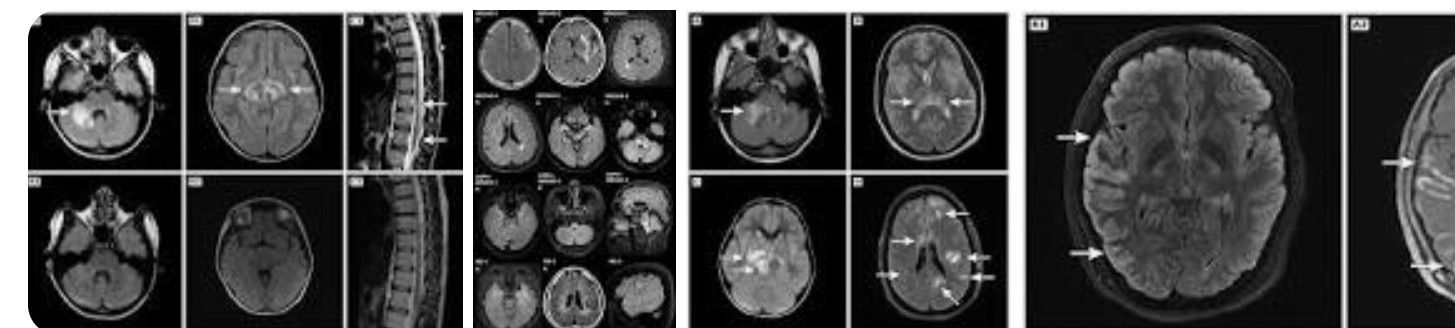

A new study set out to assess potentially distinct immune mechanisms underlying multiple sclerosis and myelin oligodendrocyte glycoprotein-associated disease. The findings point to distinct features of circulating cellular immune profiles in children with MS and MOG-associated disease and provides novel insights into early immune mechanisms that may be involved in each of these conditions.

Approximately 20 to 30 percent of children with acquired inflammatory demyelinating syndromes have MS. Another 30 percent harbor antibodies against MOGAD. While MS and MOGAD can have similar features, differences in response to immune therapies point to distinct underlying immune mechanisms.Researchers at the University of Pennsylvania, the Center for Applied Genomics at the Children’s Hospital of Philadelphia, McGill University, in Montreal, the Hospital for Sick Children, in Toronto, and the University of Manitoba, in Winnipeg, analyzed blood cells collected from patients with ADS prior to the application of immune therapy, as well as from healthy controls. CITE-Seq profiling recovered a total of 104,200 single cells with equal contribution from 24 children (six healthy donors; six with ADS but neither MS nor MOGAD; six with MOGAD; and six with MS, ascertained with long-term follow-up).Comparative analyses revealed features within the T-cell compartment that differed between children with MS and MOGAD. Specifically: